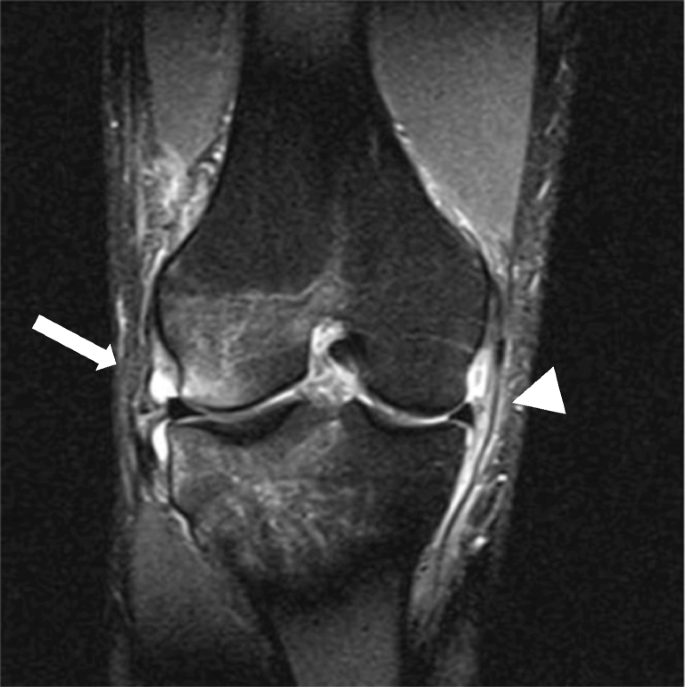

관절은 우리 몸의 운동 범위를 안전하고 넓게 가동할 수 있는 역할을 하게 됩니다. 이러한 관절 중에 팔의 중심부인 팔꿈치와 다리의 중심부인 무릎의 경우에는 여러 인대와 근육, 기타 구조물 들이 위치하고 있습니다. 무릎이 Lateral 에서 Medial 로 큰 충격을 받게 되면(Valgus force) 내측에 있는 구조물 들이 영향을 받게 되는데 아래 그림과 같은 매커니즘으로 손상을 입게 됩니다.

붓기가 빠진 후에 수술을 하는 경우가 많으며, MCL 과 medial meniscus의 손상여부를 파악 후에 ACL recon 등의 수술을 시행하면서 함께 시행해 볼 수 있겠습니다. (운동 선수들의 경우 기능적 회복을 위하여 수술을 필요로 하는 경우가 많습니다.)